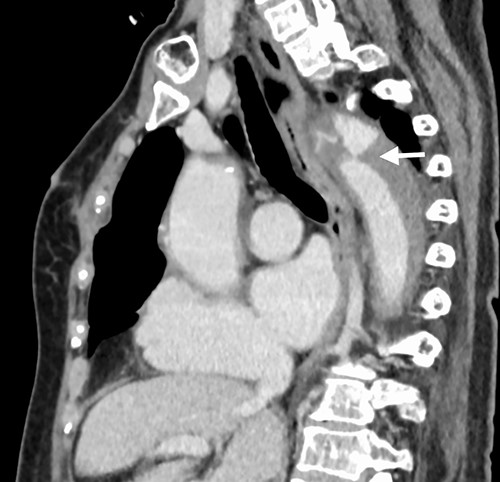

A 76-year-old woman with a giant retroperitoneal tumor was scheduled for surgical resection (Fig. 1). However, preoperative examination revealed severe aortic valve stenosis (AS); therefore, the patient first underwent minimally invasive aortic valve replacement (MICS-AVR) for severe AS. In this operation, we approached the surgical site through the right third intercostal space, and cardiopulmonary bypass was established with right femoral arterial and venous cannulation. PERCEVAL (Livanova, London, UK), a sutureless valve, was used as the artificial valve. Five days post-operatively, she complained of back pain, and a computed tomography (CT) scan revealed bleeding in the tumor and tumor growth. There were no findings of aortic dissection. A peripheral branch of the left third lumbar artery seemed to be the bleeding site; thus, lumbar artery transcatheter artery embolism (TAE) was performed. Although the bleeding stopped, early surgery was considered to be appropriate for the tumor. Therefore, retroperitoneal tumor resection and left nephrectomy were performed on the 12th post-operative day. Four days after tumor resection, the patient suddenly experienced persistent back pain again. CT revealed a Type B AAD. The aorta was dissected from the distal part of the left subclavian artery (LSA) to the level of the right renal artery, and an ulcer-like projection (ULP) was observed at the distal arch (Fig. 2). Although conservative treatment was started immediately, her back pain persisted and follow-up CT revealed slight growth of the ULP. Thus, we decided to perform thoracic endovascular aortic repair (TEVAR) using Valiant (Medtronic, Minneapolis, USA). Before the TEVAR procedure, we performed extra-anatomical bypass from the left common carotid artery to the LSA using PROPATEN (Gore, USA). The Valiant was deployed from Zone2 to just above the celiac artery (Fig. 3). The post-operative course was uneventful, and the patient was discharged without any complications. One year after discharge, CT showed that the aorta was remodeled almost as before (Fig. 4).